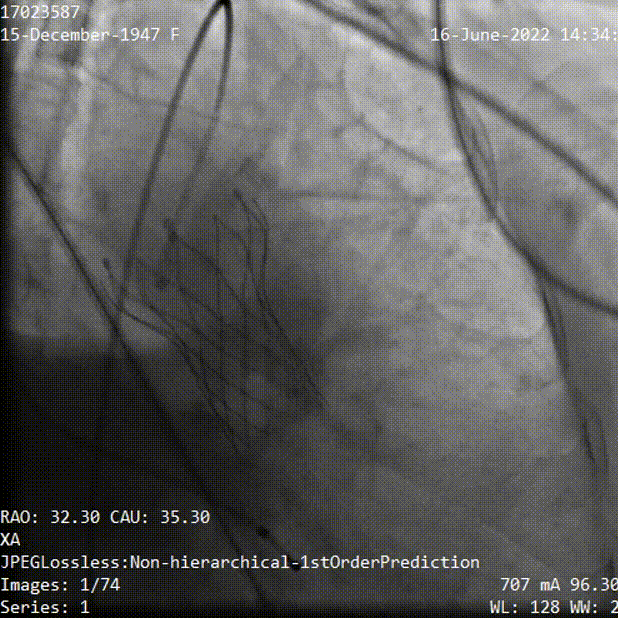

主动脉根部造影,主动脉瓣开放受限,中度反流,采用20mm球囊预扩,有明显腰征,无造影剂渗漏,测压差70mmHg左右。

主动脉根部造影

球囊预扩